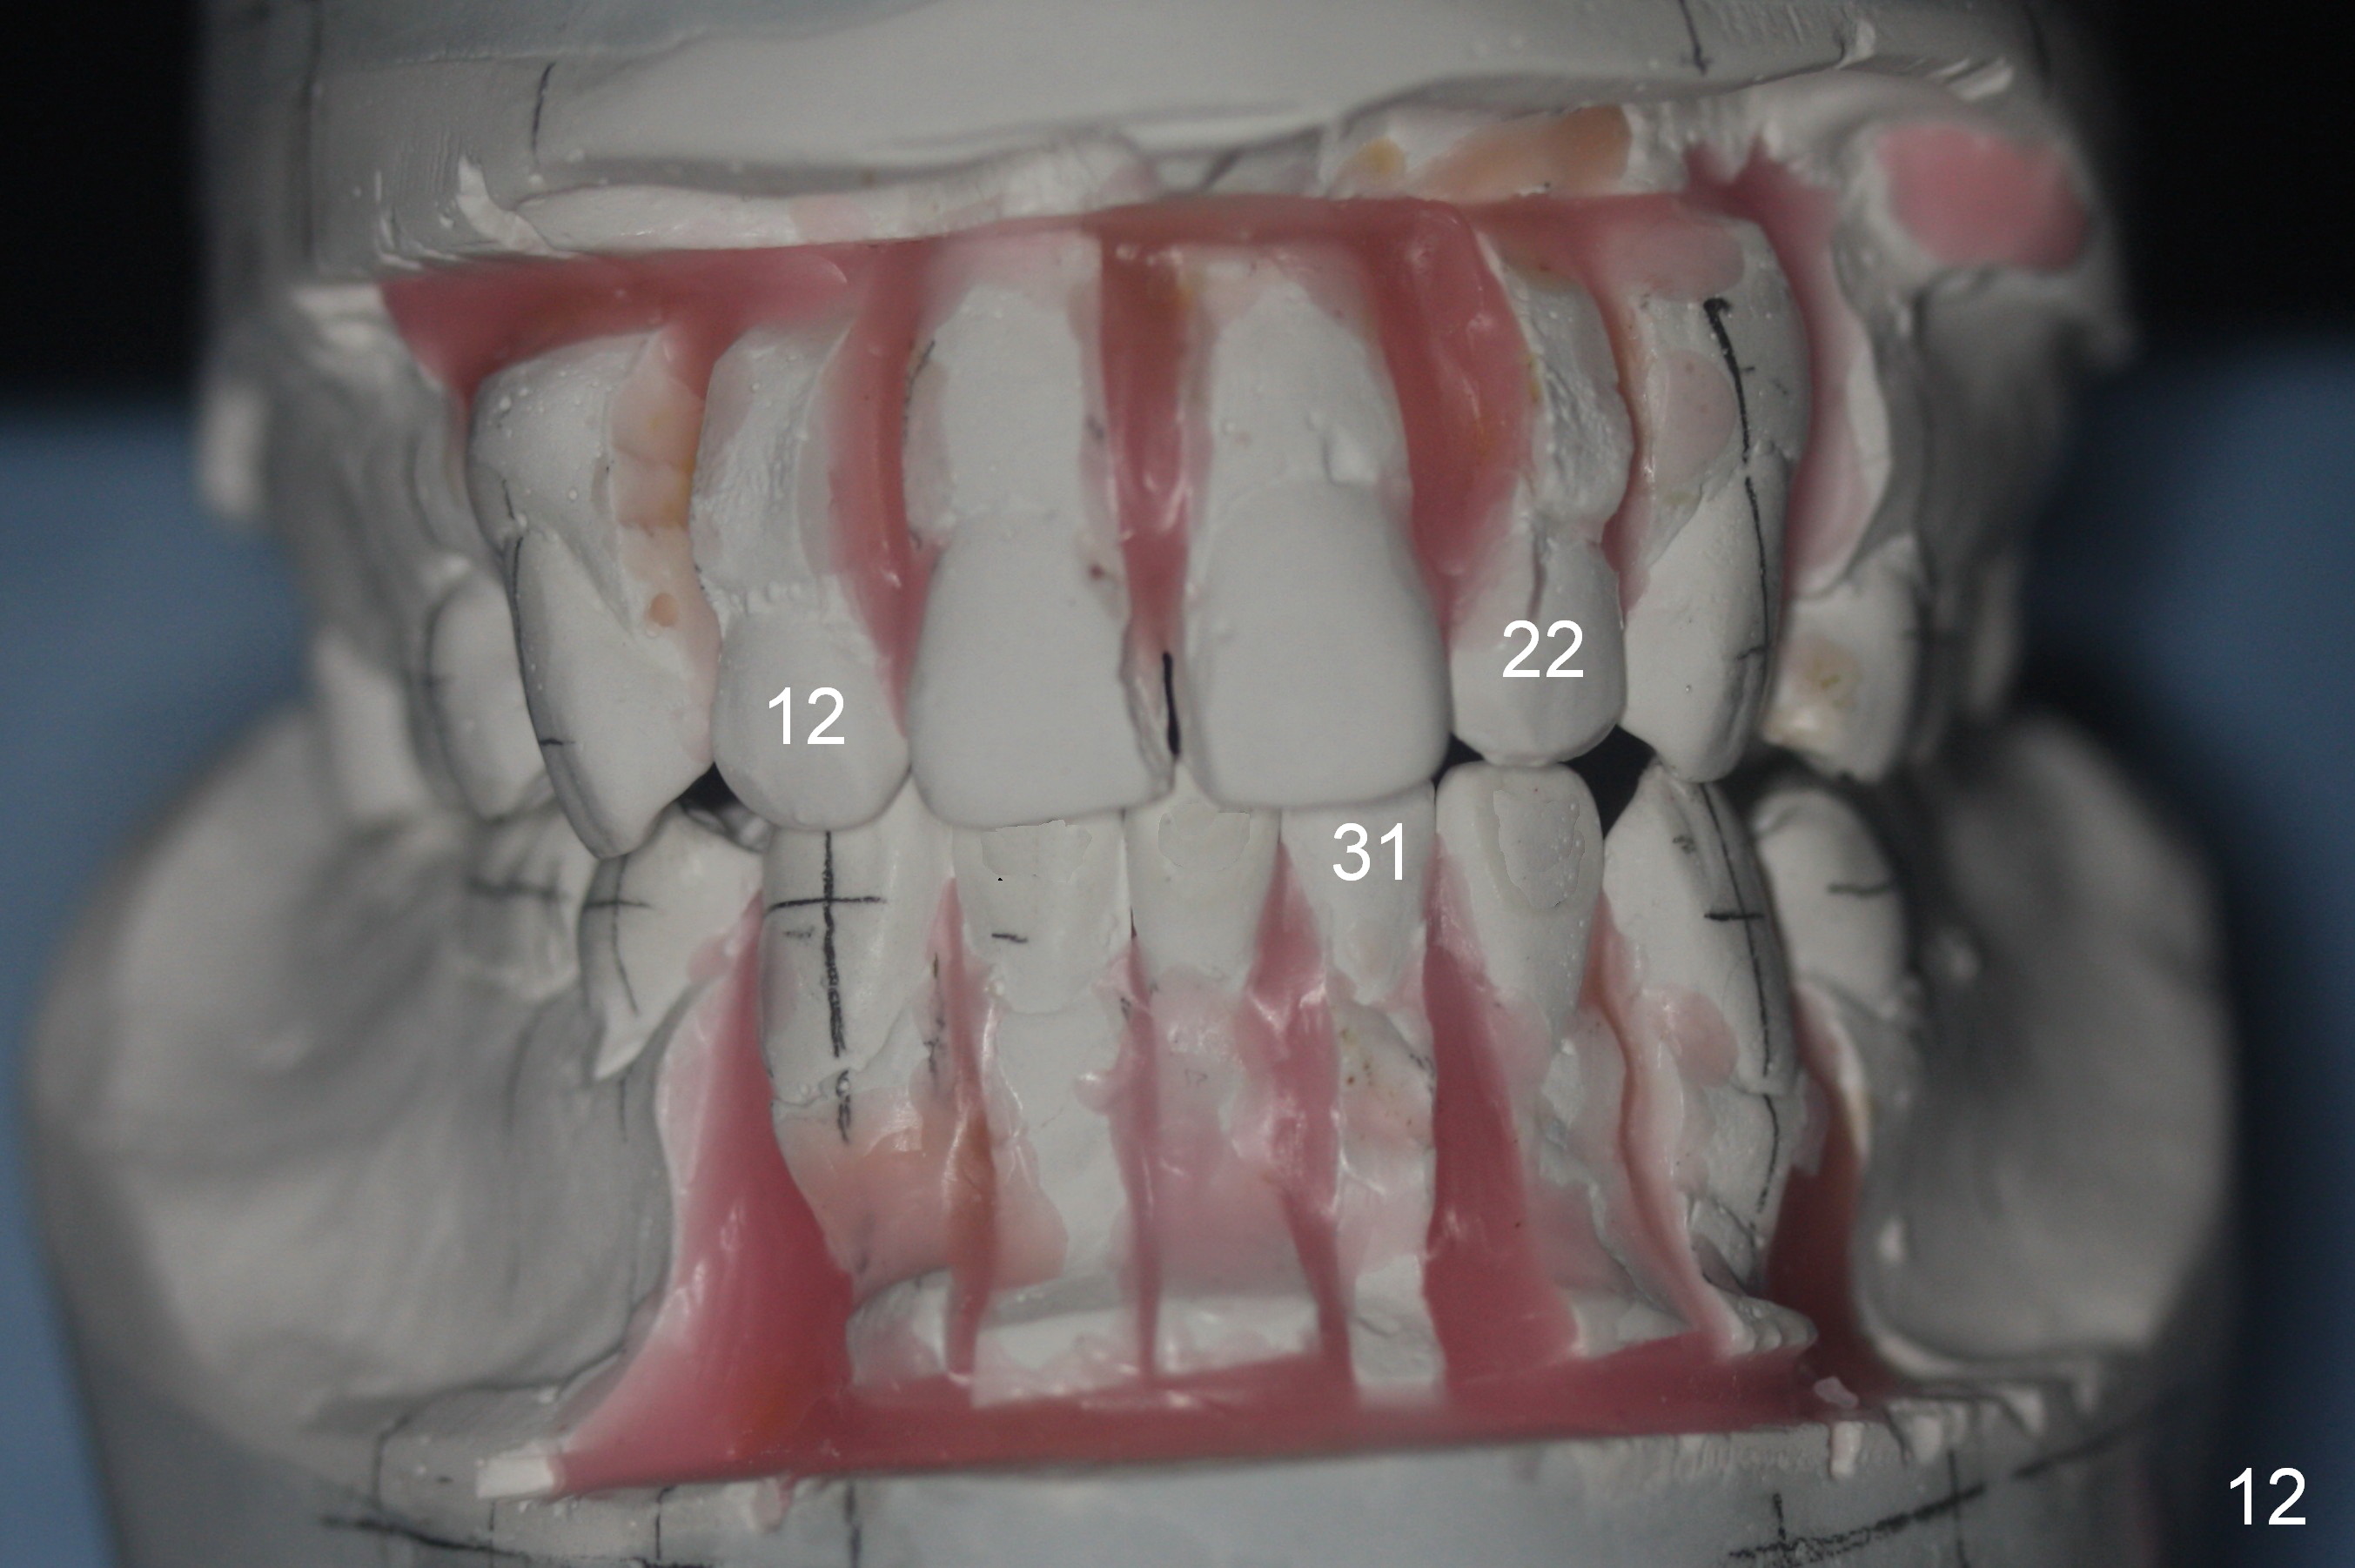

A 37-year-old man requests orthodontic treatment for severe crowding with 3 blocked-out incisors (Fig.1-5: 12,22,31 (International numbering, pronounced one two, two two and three one)). The upper and lower arches are pointed (Fig.4,5). The best option is extraction of 4 bicuspids (Fig.11-15).

His profile is convex with lip strain. After alignment of the anterior teeth, check the facial profile to determine whether it is necessary to distalize the anterior teeth or not. If it is, the distalization will be done with the aid of an implant at 47 (Fig.1,5 (residual roots)) and 3 mini-implants at the 3 other quadrants. An extra mini-implant will be placed at the upper right quadrant to intrude 17 (Fig.1 arrow).

There may be limited space for placement of these blocked out incisors. Do not have to place them at the time of bracketing until space has been created by arch wire sequence and open coil spring. It would be ideal to use labial torque brackets or place brackets upside down (Jenny's idea). In fact, the patient finishes ortho treatment in an orthodontist's office without intrusion of 17. Magicore will be placed at 47 to intrude 17 or simply for restoration.